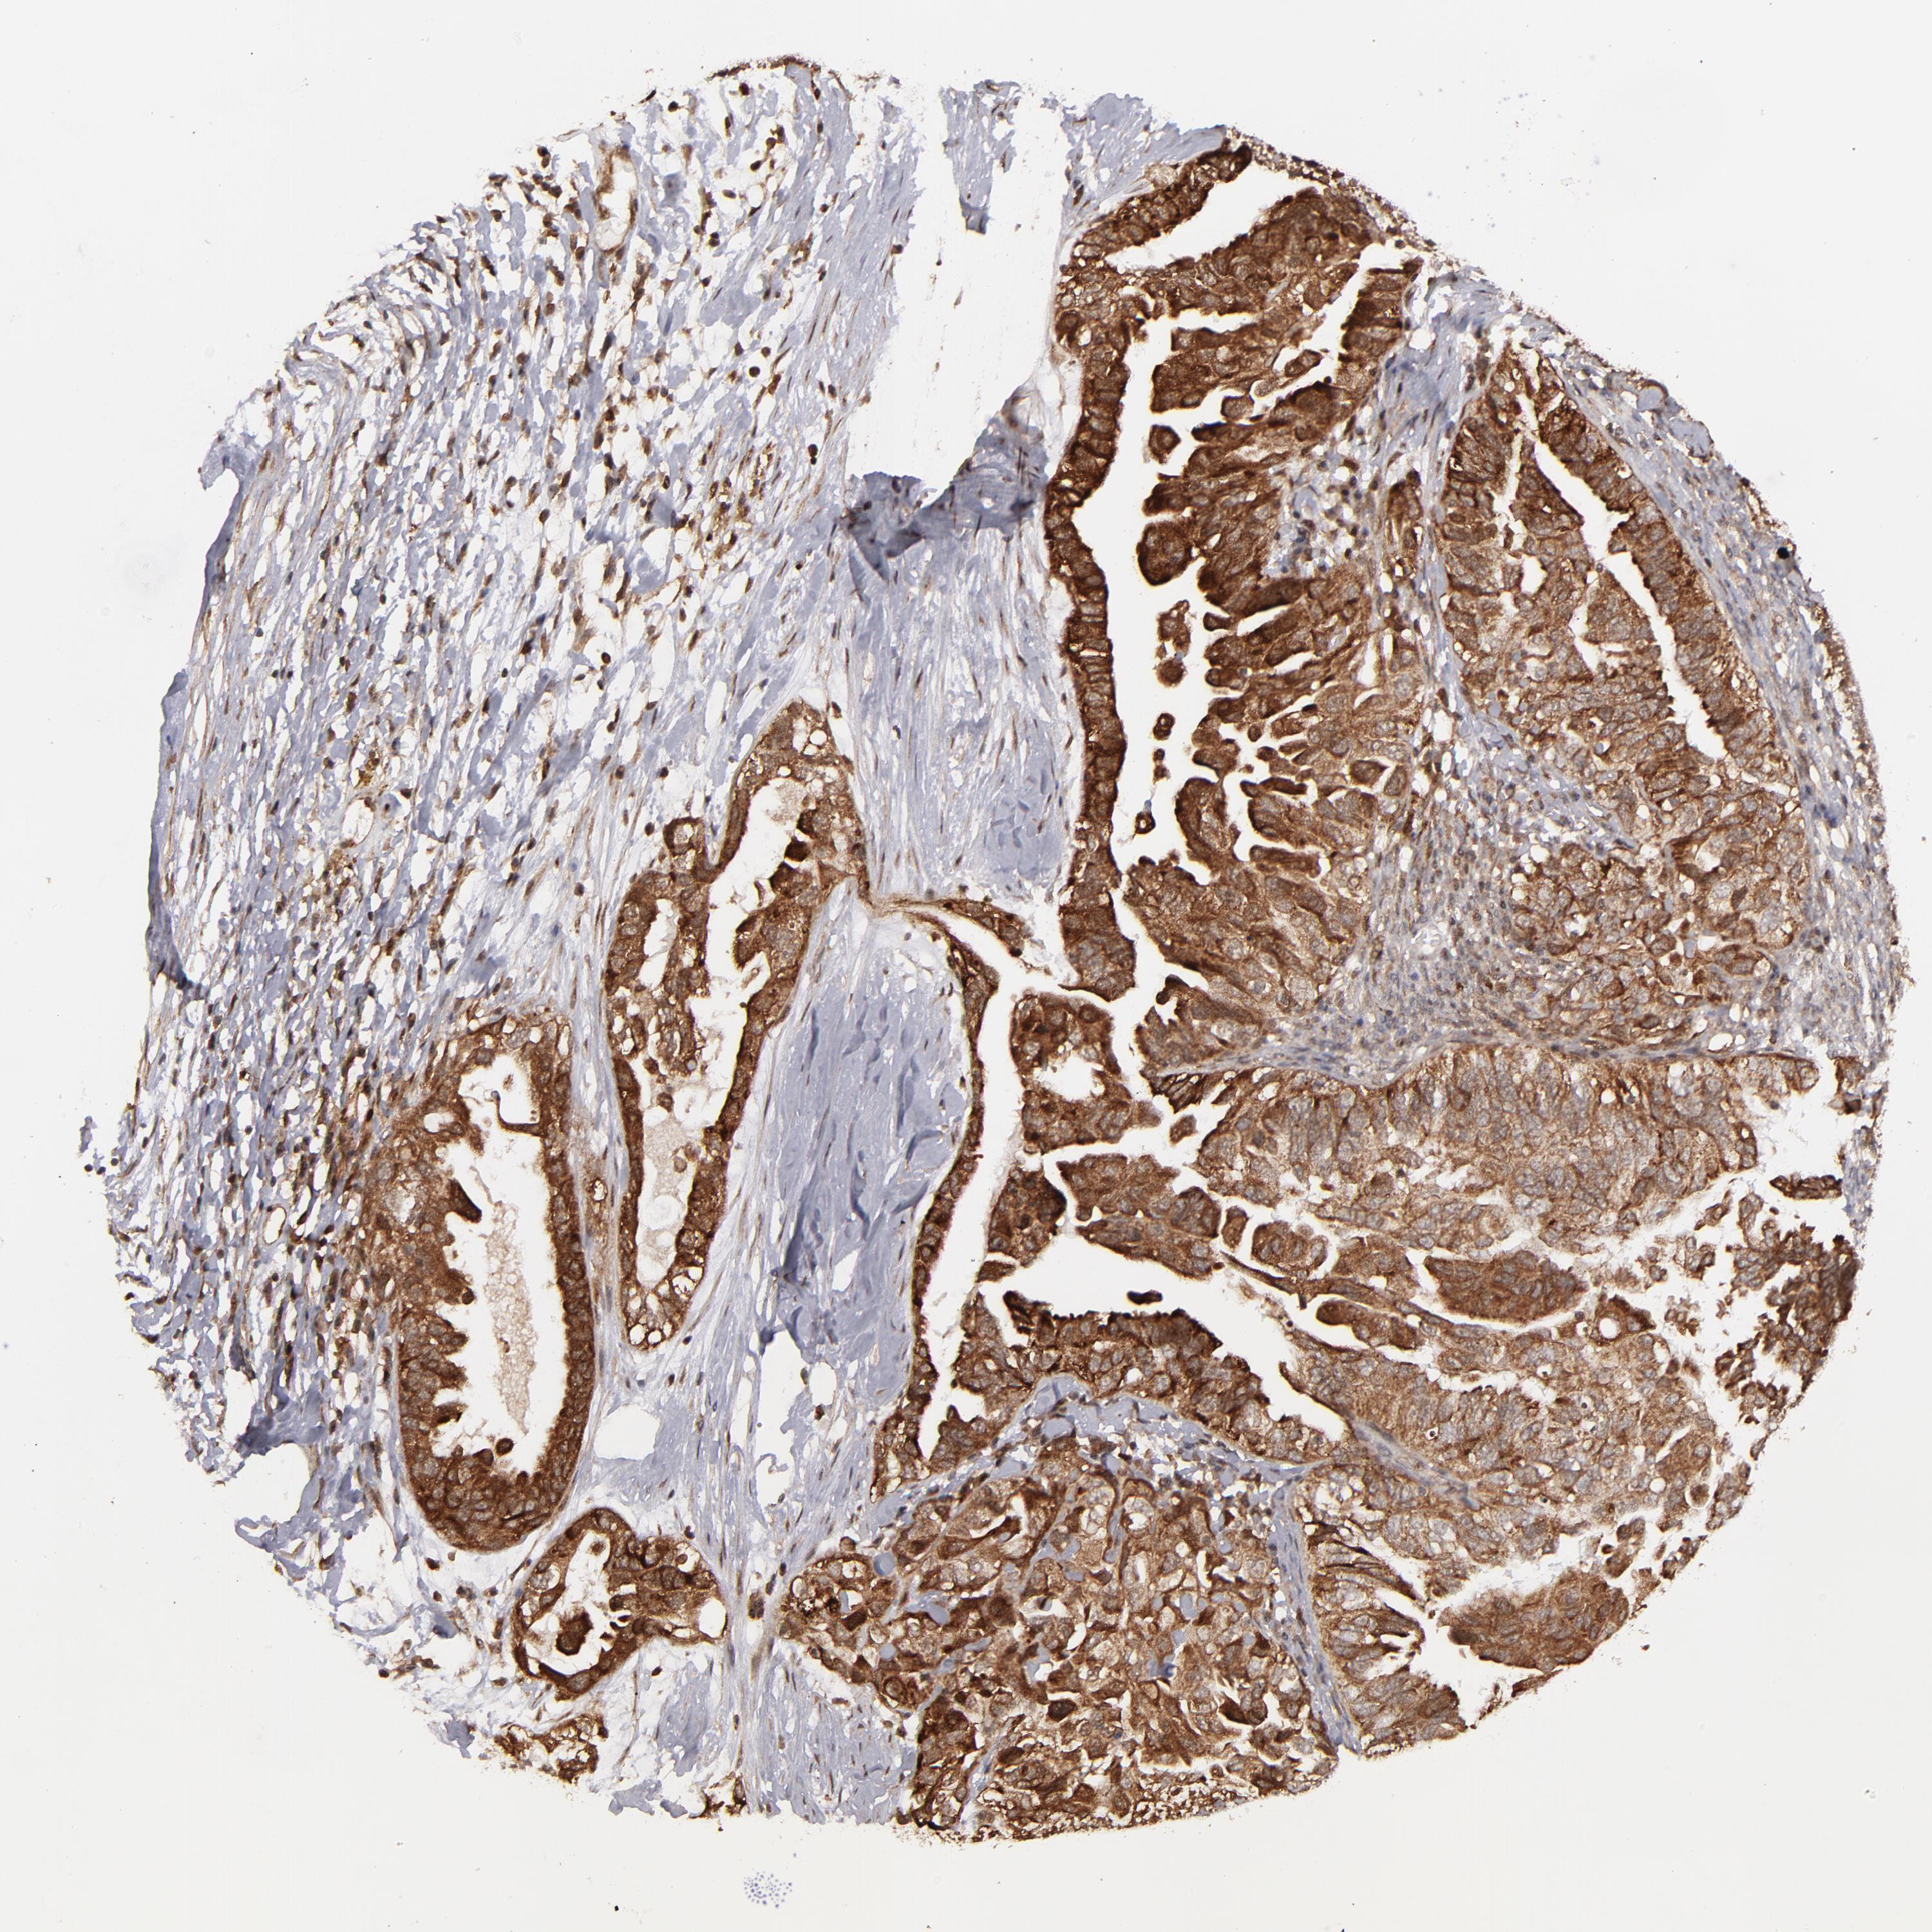

OVARIAN CANCER - Protein expressioni

A mouse-over function shows sample information and annotation data. Click on an image to view it in a full screen mode. Samples can be filtered based on level of antibody staining by selecting one or several of the following categories: high, medium, low and not detected. The assay and annotation is described here.

Note that samples used for immunohistochemistry by the Human Protein Atlas do not correspond to samples in the TCGA dataset.

Antibody stainingi

Antibody staining in the annotated cell types in the current human tissue is reported as not detected, low, medium, or high, based on conventional immunohistochemistry profiling in selected tissues. This score is based on the combination of the staining intensity and fraction of stained cells.

Each image is clickable and will lead to virtual microscopy that enables deeper exploration of all samples and also displays staining intensity scores, fraction scores and subcellular localization as well as patient and tissue information for each sample.

Antibody HPA003067

Staining

High

Medium

Low

Not detected

Intensity

Strong

Moderate

Weak

Negative

Quantity

>75%

75%-25%

<25%

None

Location

Nuclear

Cytoplasmic/membranous

Cytoplasmic/membranous,nuclear

Cystadenocarcinoma, serous, NOS

Cystadenocarcinoma, mucinous, NOS

Carcinoma, endometroid